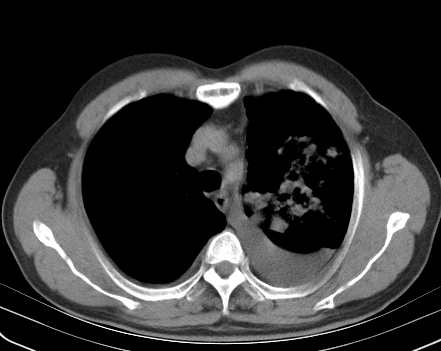

以下是引用老爱克斯新网客在2008-7-31 6:30:00的发言:[br]左肺上叶大片状病灶,左肺上叶支气管狭窄呈鼠尾状,左肺门增大,纵隔内见肿大淋巴结,左侧胸腔积液,余肺清晰。左肺中心型肺癌淋巴结转移,

以下是引用zjb在2008-7-31 6:32:00的发言:[br]左侧中心性肺癌 阻塞性肺炎 肺不张 胸腔积液 建议气管镜

以下是引用zjzjr在2008-7-31 8:45:00的发言:[br]考虑左侧中心性肺癌伴阻塞性肺炎,左肺上叶肺不张,纵隔淋巴结转移;左侧胸腔积液。建议行纤支镜检查。

以下是引用sdzyy在2008-7-31 8:47:00的发言:[br]病灶较治疗前有所进展,胸水增多, 左侧中心性肺癌 并 阻塞性肺炎 肺不张 胸腔积液 可能性大; 建议气管镜检查。 [br] [br]